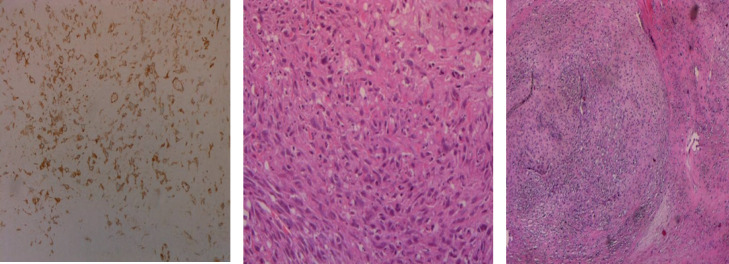

Background: Malignant triton tumors (MTT) are subtype of malignant peripheral nerve sheath tumor (MPNST) which develop from Schwan cells of peripheral nerves or within neurofibromas, and shows rhabdomyoblastic differentiation. It is a rare soft tissue tumor with poor prognosis.

Case presentation: The patient was complaining of an 8 months long progressive right shoulder pain and swelling at the posterior lateral area of the shoulder. As accurate diagnosis is crucial in such case, investigations that included x-rays and magnetic resonance imaging (MRI) demonstrated an soft tissue tumor involving the right shoulder area leading to the differential diagnosis of aggressive soft tissue tumor which laid down the plan of an open incisional biopsy to be reported histopathological as a case of Malignant Triton Tumor which is a very rare and aggressive sarcoma originates from the peripheral nerve sheaths as it is subtype of malignant peripheral nerve sheath tumors after which excision of the entire tumor with safety margin was performed and referred for adjuvant chemotherapy.